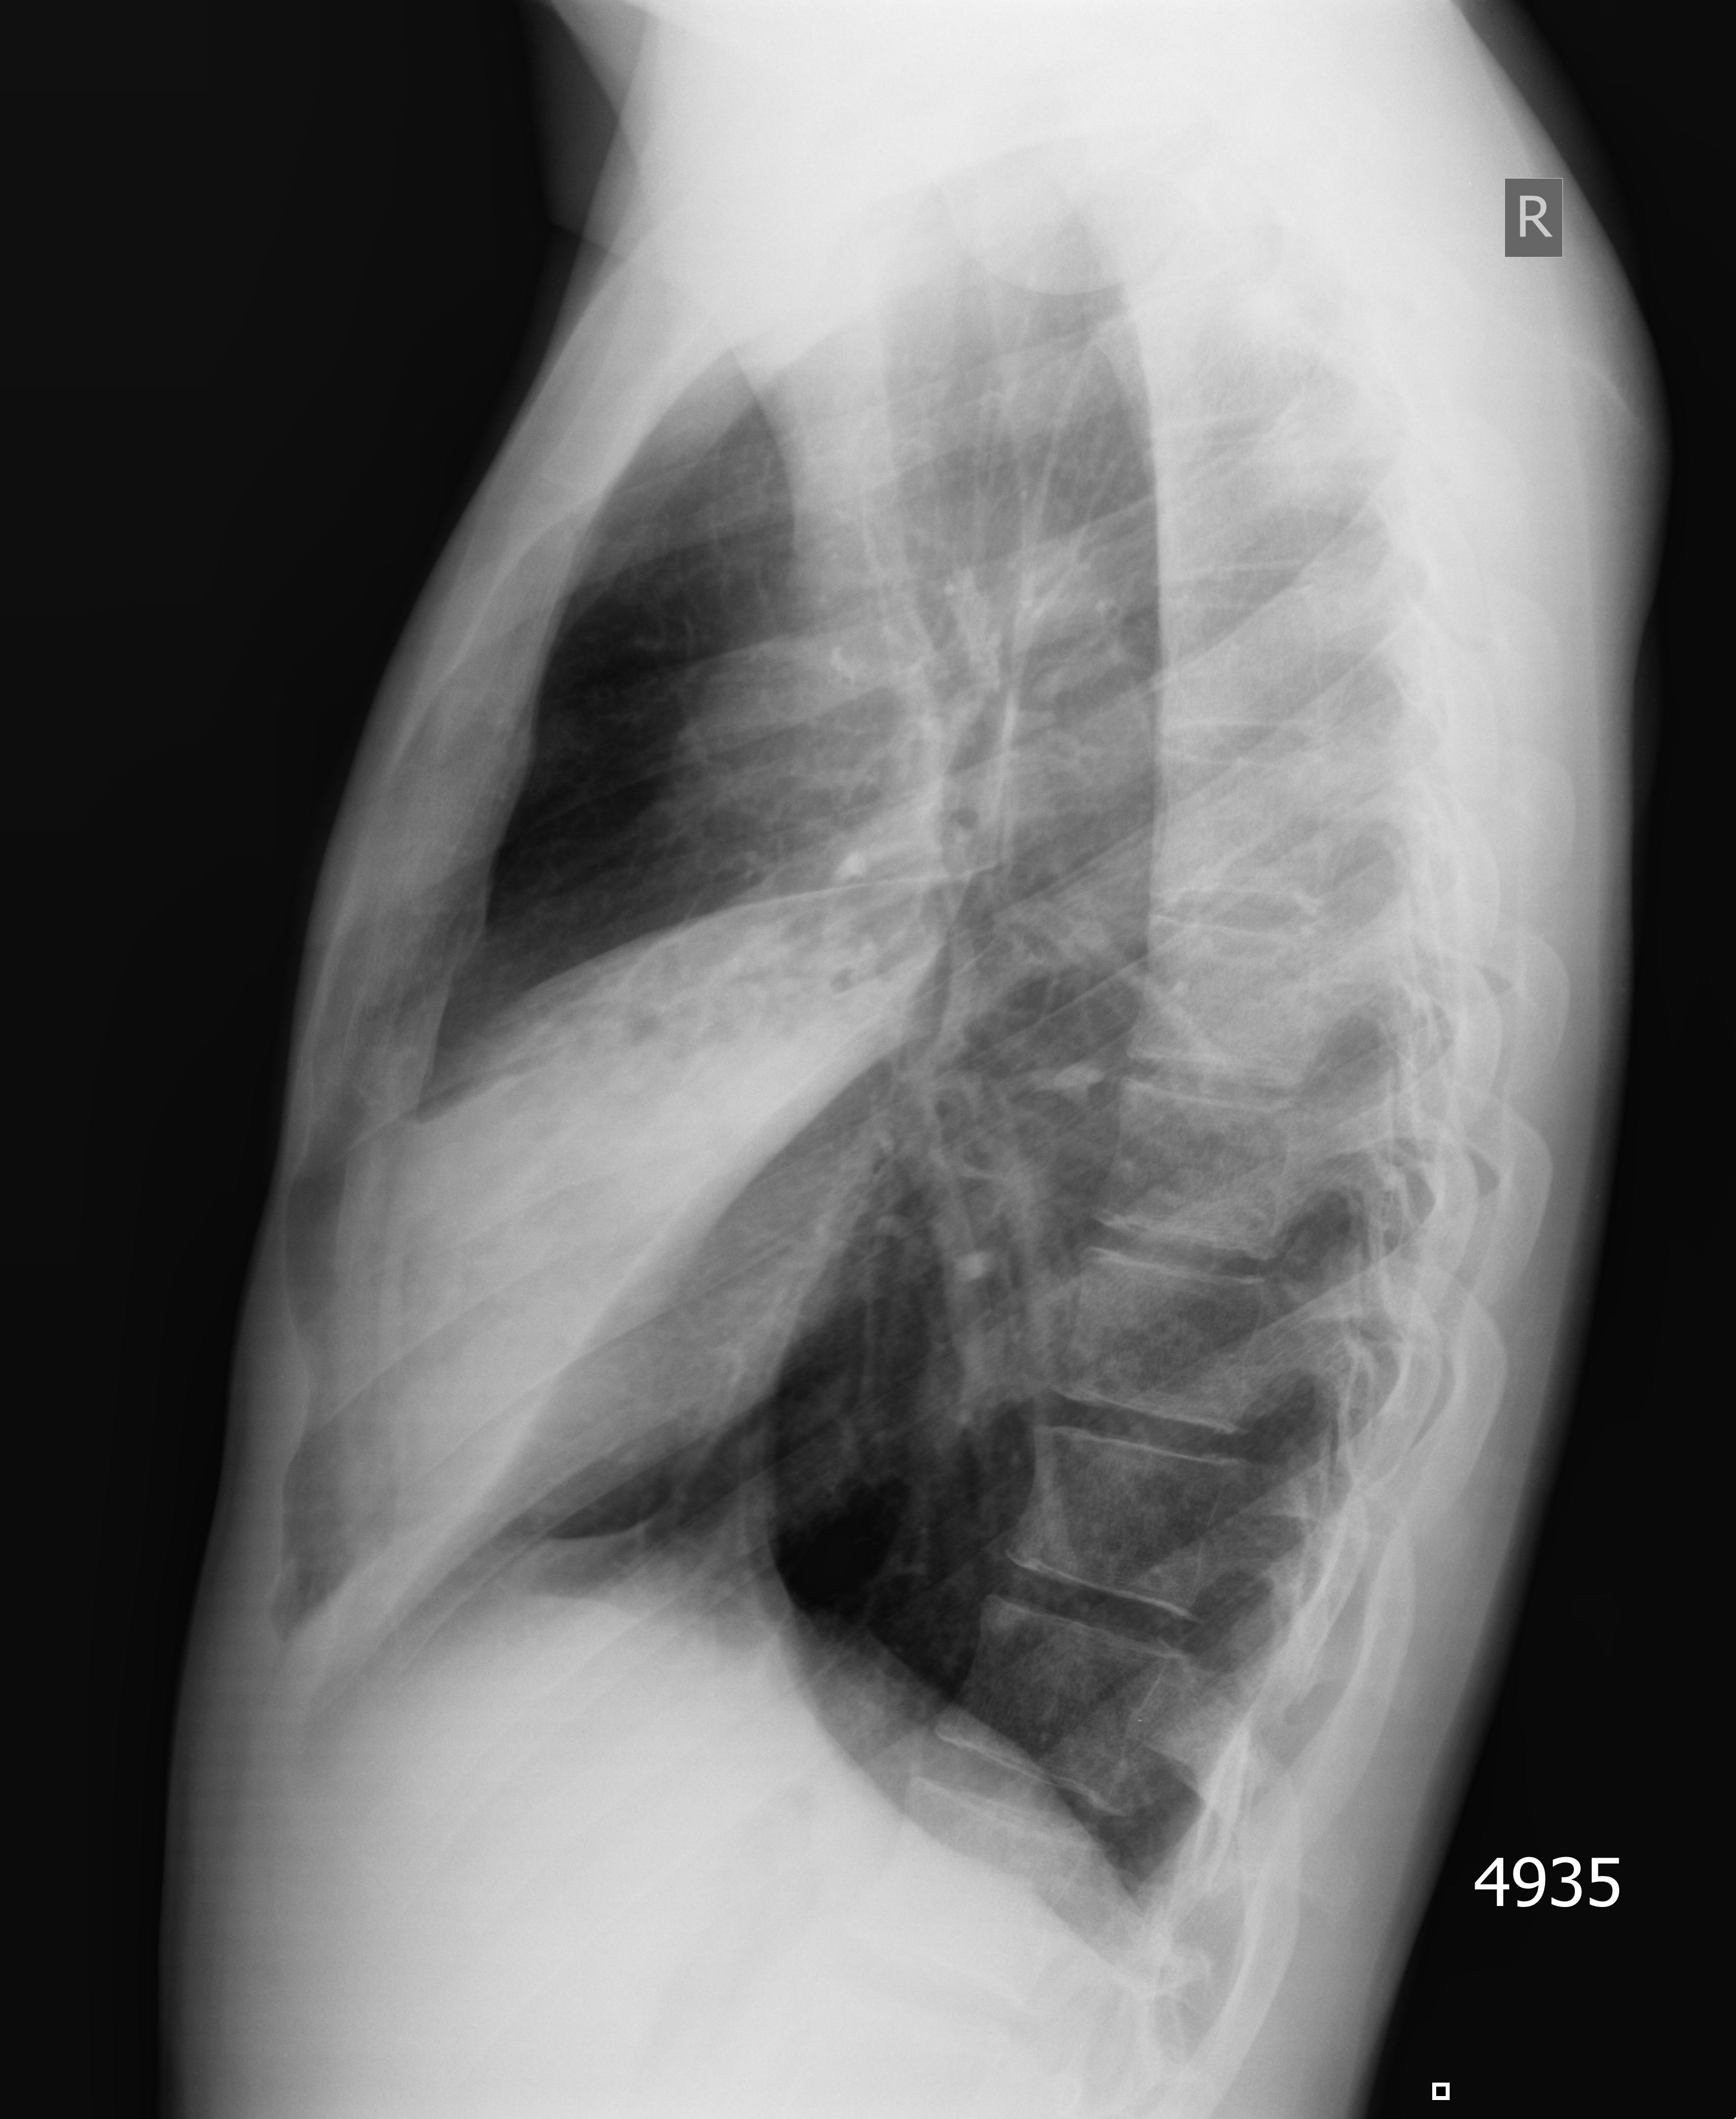

Правостороння пневмония, УЗИ и рентген

Молодой парень. Высокая температура, сухой кашель.